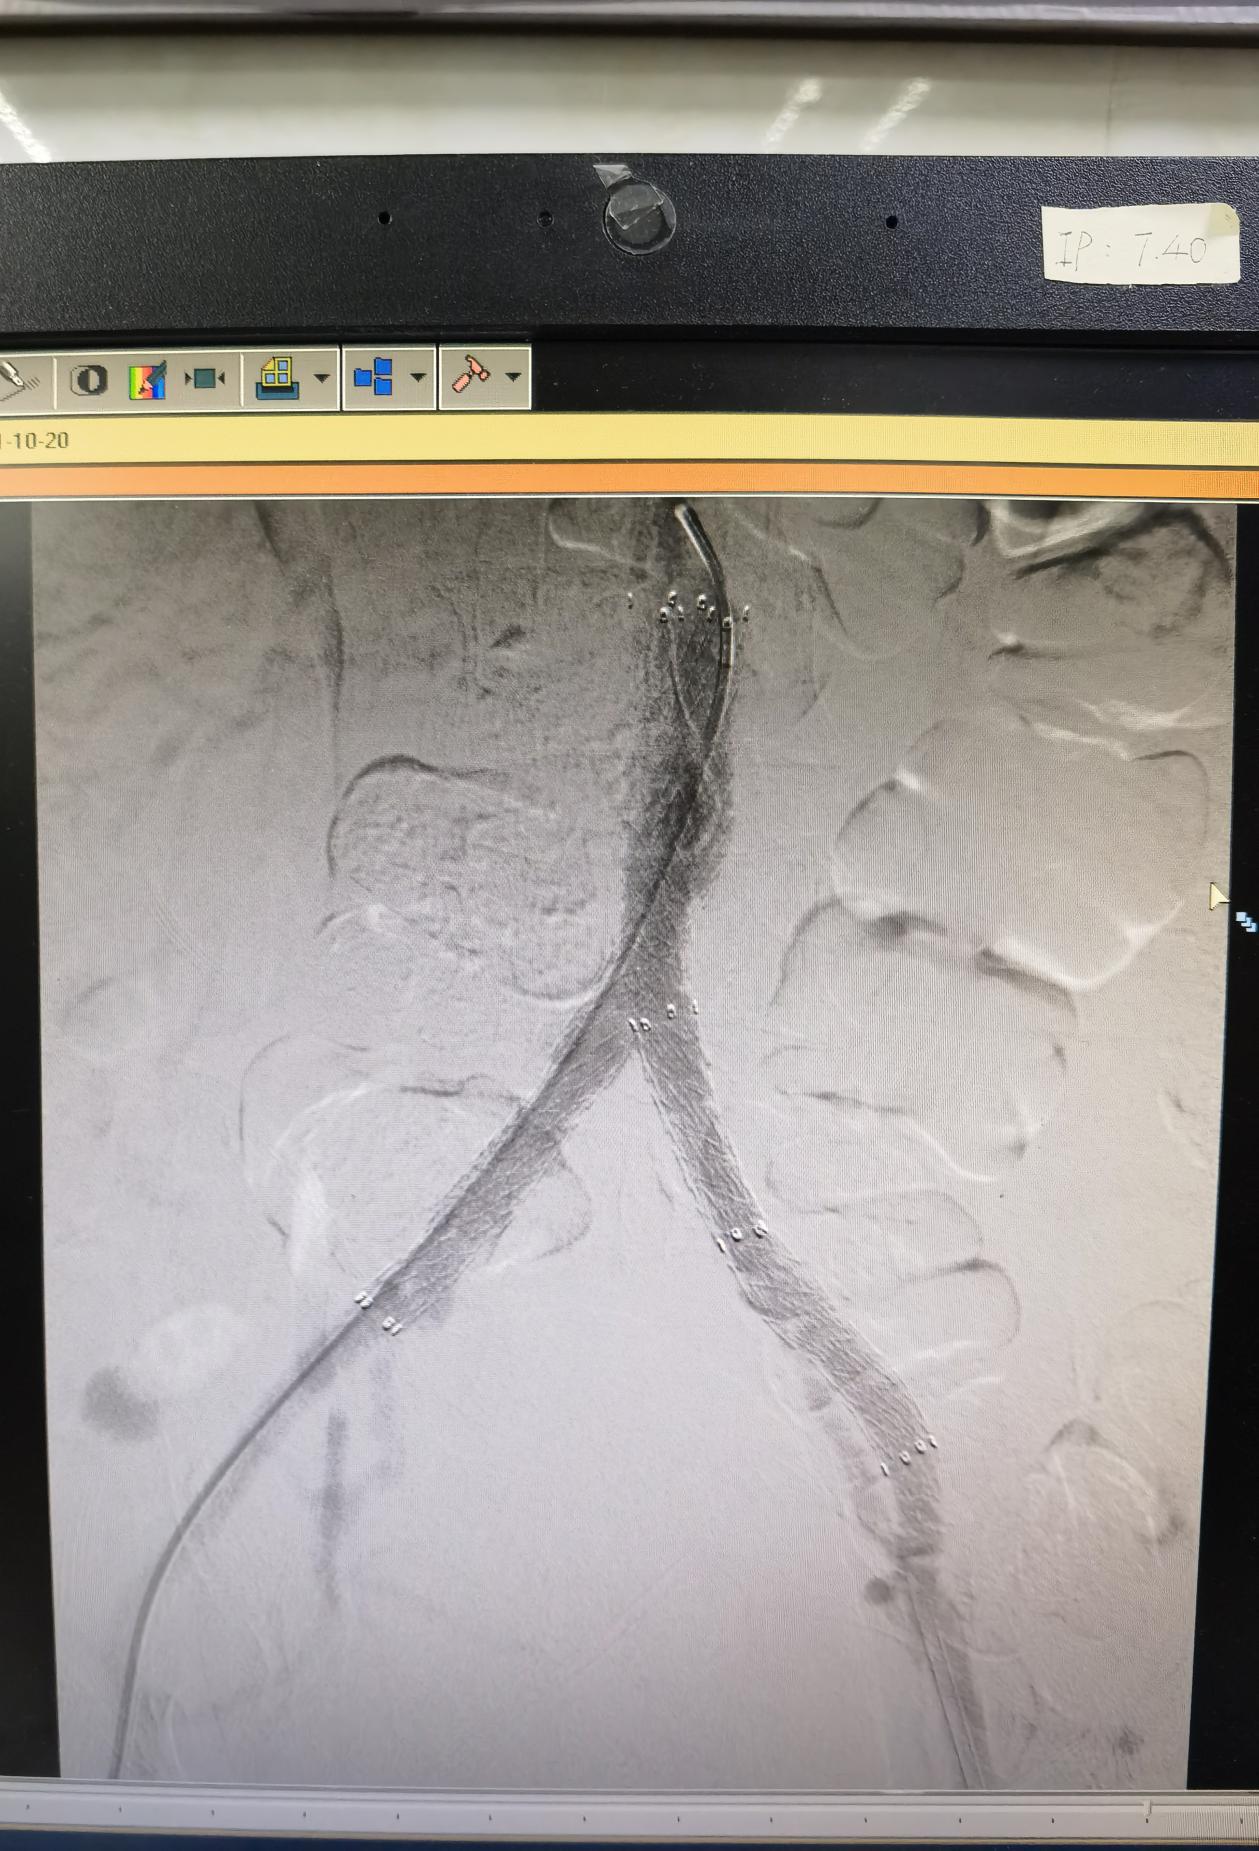

5月20日下午,心脏大血管外科副主任医师唐开维与科室副主任轩永波顺利为老张完成了手术。术中造影提示老张左髂总动脉闭塞,局部多发斑块,无血流通过。腹主动脉下段狭窄约80%,右髂总动脉中上段有斑块,造成局部狭窄50- 60%,左髂总动脉起始部后闭塞。老张病情复杂,两位专家先从左侧多次尝试使导丝导管突破闭塞段,最后成功突破进入腹主动脉真腔内。考虑老张局部动脉斑块多,为预防破裂,他们进行逐级扩张,定位良好后释放支架。为处理老张腹主动脉下段狭窄的问题,他们沿左侧、右侧导丝同时送入血管支架,使用Kissing技术成功释放两枚支架。手术很成功,再次造影时显示老张体内支架位置良好,其内血流通畅,支架无明显狭窄。

(图片4:术后造影显示恢复血流的血管)